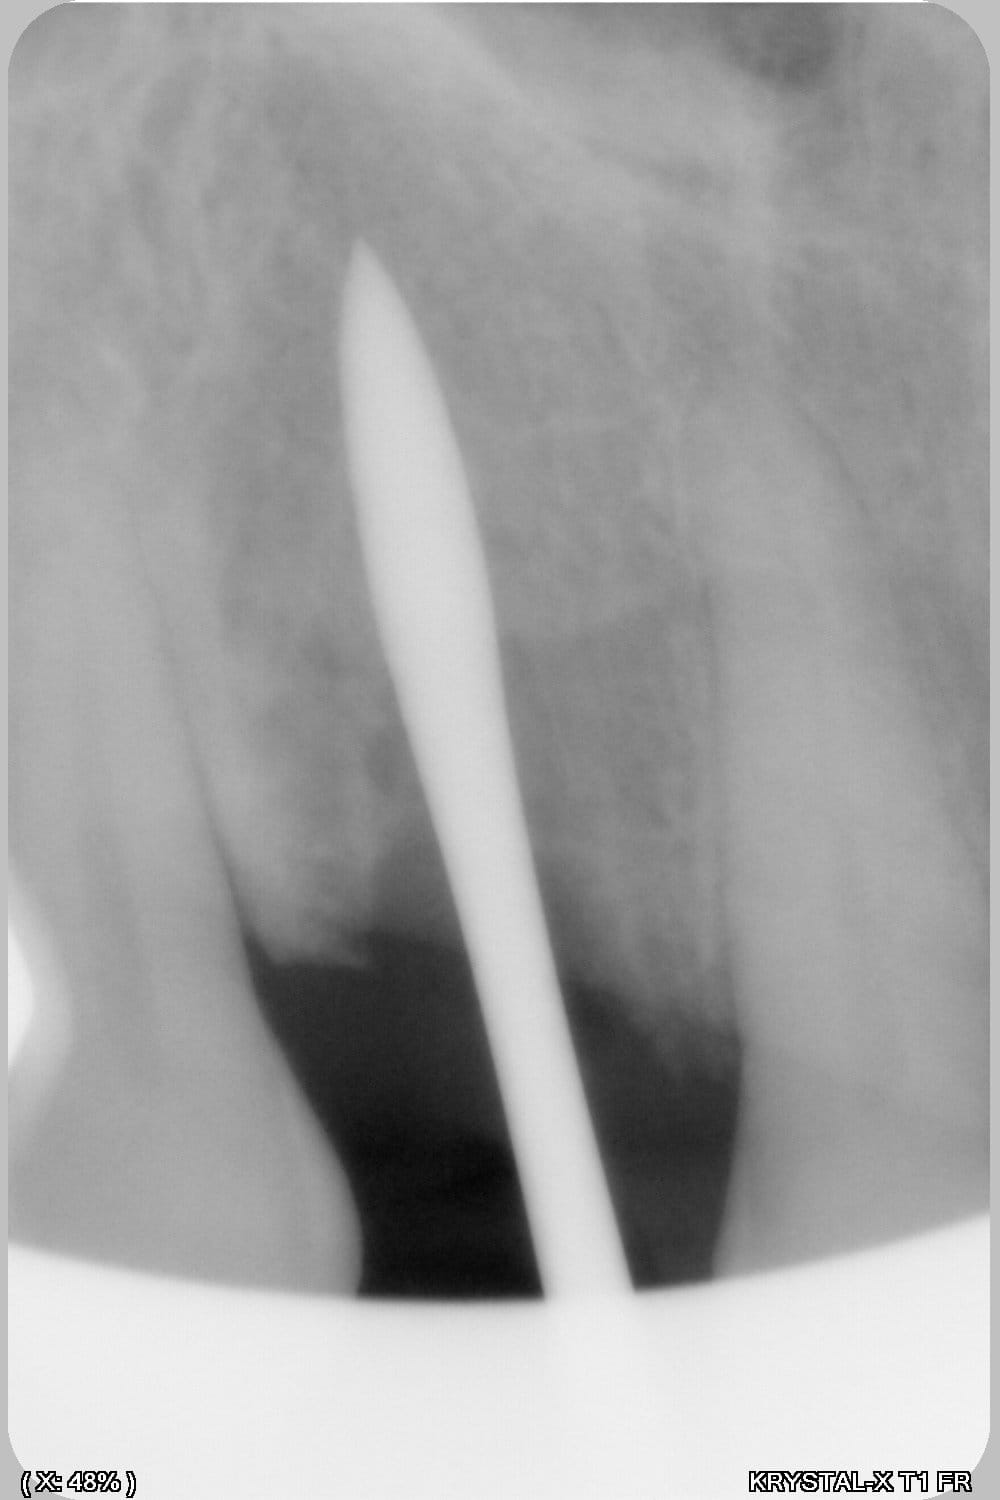

Thomas, tu as un plan pour guider dans un cas comme ça?

ou comment remplacer 12 avec soucis vestibulaire, par un implant, sans greffe, sans ROG, juste avec les mimines....?

Et bien pas de cone beam, pas de scanner,pas de panoramique...pour ne pas irradier l'os...et franchement je ne vois pas en quoi un guide me servirait dans un cas comme ça.

Objectivement un guide ne serait pas assez précis pour faire cela à l'aveugle